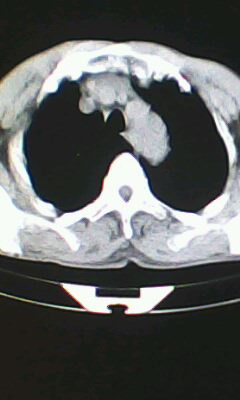

胸廓呈桶状,双膈低平,肺实质及纵隔未见明显异常密度灶考虑肺气肿.

肺气肿

以下是引用ctkz987在2010-5-5 21:30:00的发言:[br]胸廓呈桶状,双膈低平,肺实质及纵隔未见明显异常密度灶考虑肺气肿.

弥漫性肺气肿 但内胆管轻度扩张

临床诊断:copd

慢阻肺是临床诊断,未见明显异常。